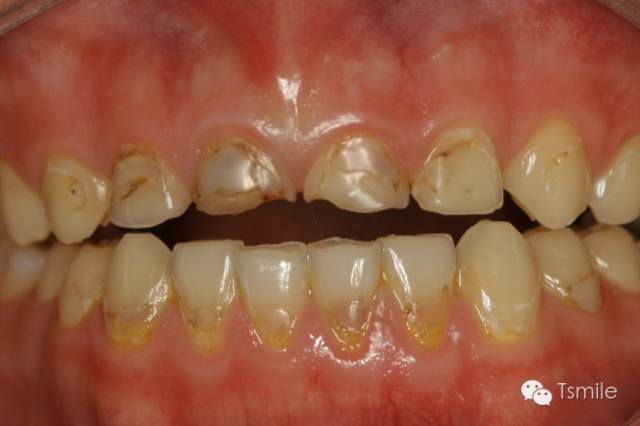

圖4: 神經(jīng)性貪食癥導(dǎo)致的上頜前牙舌側(cè)重度磨耗

神經(jīng)性貪食癥是患者由于心理性原因在飲食后自我催吐,混有胃液的嘔吐物進(jìn)入口腔內(nèi),接觸牙齒表面,對(duì)牙齒硬組織造成嚴(yán)重酸蝕脫礦。由于患者在嘔吐時(shí)的特定體位,神經(jīng)性貪食癥導(dǎo)致的牙列重度磨耗主要發(fā)生于上前牙的舌側(cè)、或者累積上頜前磨牙的舌面。

胃食管返流病,英文名Gastroesophageal Reflux Disease,簡(jiǎn)稱GERD,是由于消化系統(tǒng)疾病導(dǎo)致胃液返流至口腔內(nèi),胃液接觸牙齒表面,胃酸對(duì)牙齒硬組織造成嚴(yán)重酸蝕脫礦。胃食管返流病導(dǎo)致的牙列重度磨耗主要發(fā)生于上頜牙齒的舌面以及下頜磨牙的頜面。胃食管返流病患者在夜間睡眠時(shí)胃液返流導(dǎo)致的牙齒酸蝕脫礦最為嚴(yán)重,由于患者的睡姿體位不同,因而造成牙齒酸蝕脫礦的部位和程度在牙弓左右兩側(cè)并不對(duì)稱。

圖5: 胃食管返流病導(dǎo)致的牙列重度磨耗